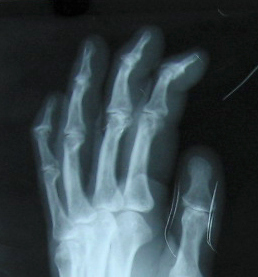

Fig.4. Lt. hand oblique view magnified for D I P joints